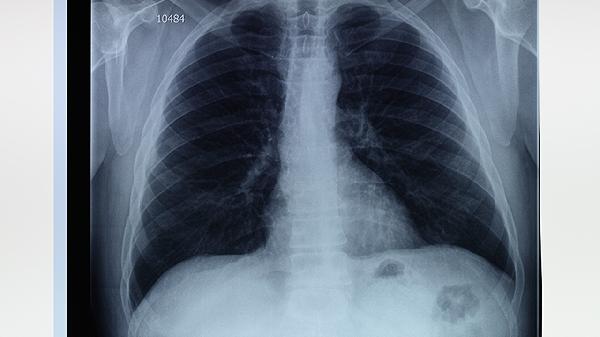

4、定期复查:肺大泡患者应定期进行胸部影像学检查,如CT扫描,监测肺大泡的大小和数量变化,及时调整治疗方案。